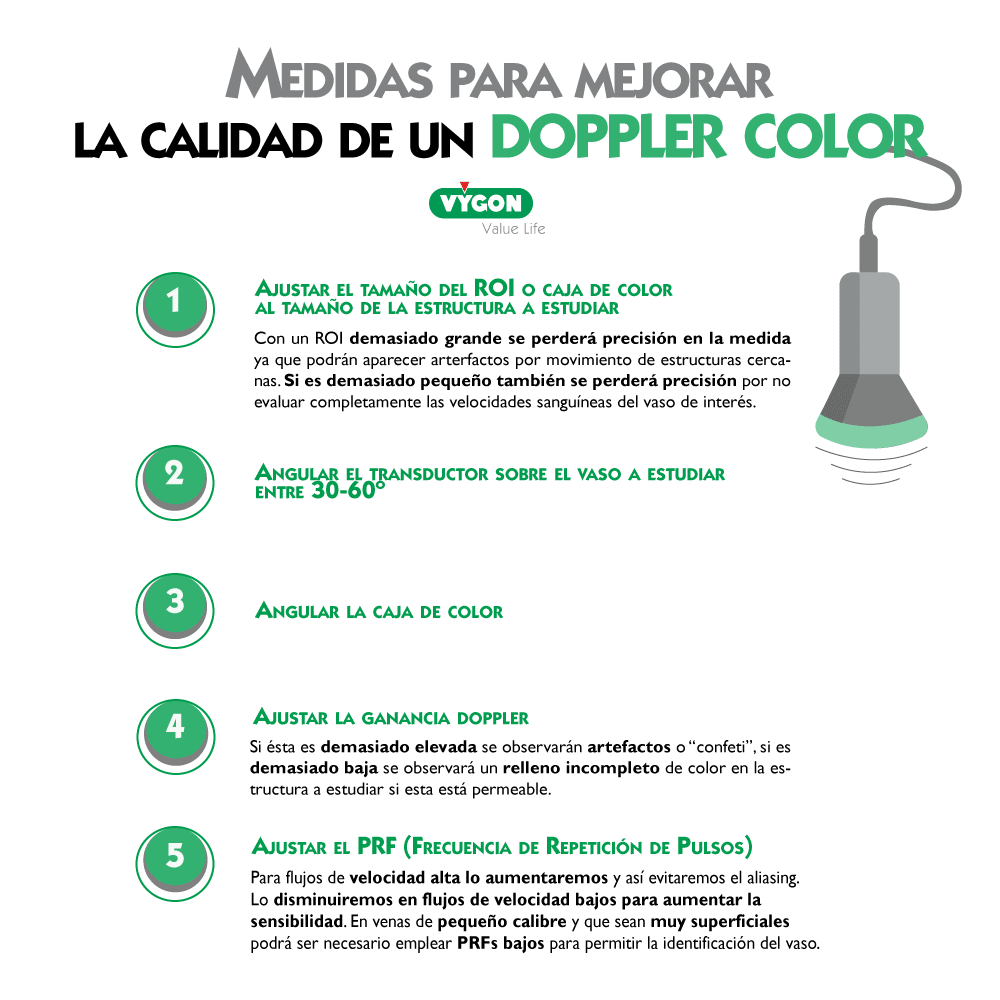

2.Cómo mejorar la calidad del análisis del doppler color

Existen varias manipulaciones y ajustes que puede hacer el operador para poder mejorar el análisis del doppler:

Cuando se estudia un vaso longitudinalmente con modo doppler color, puede ser útil emplear la opción de angulación de la caja de color, de tal manera que ahora los ultrasonidos se emitan angulados desde la sonda.

Esto facilita la identificación del vaso, sin tener que bascular la sonda en la piel del paciente. Teniendo en cuenta la posición de la muesca del transductor respecto a la pantalla y la angulación del ROI, podremos discernir la dirección del flujo estudiado mediante la misma regla: el flujo que se acerca al transductor será de color rojo y el que se aleja de color azúl.